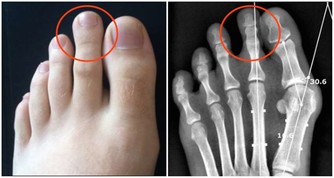

5. 沒有計劃的非科學鍛煉

鍛煉是一個循序漸進的過程,想要通過深蹲練就翹臀,應該逐漸增加運動量;而不是某天心血來潮,連續做一百個蹲起。突然加大運動量,或是熱身運動不到位,都會對肌肉組織造成不小的壓力,甚至是誘發痔瘡。條件允許時,最好能請專業人士為自己量身打造健身計劃,在專人看護與輔導下使用健身器械。醫生提醒:痔瘡患者的數量龐大,但也不要因為這類疾病比較普遍而不去看醫生。